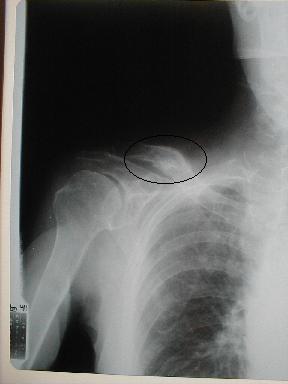

| 12月26日受傷後77日目 |

受傷者が高齢で、なおかつ固定を嫌い早期〔30日間)に除去を願った為変形治癒となった。しかし、上腕挙上も可能で、日常生活動作には何ら支障はない。